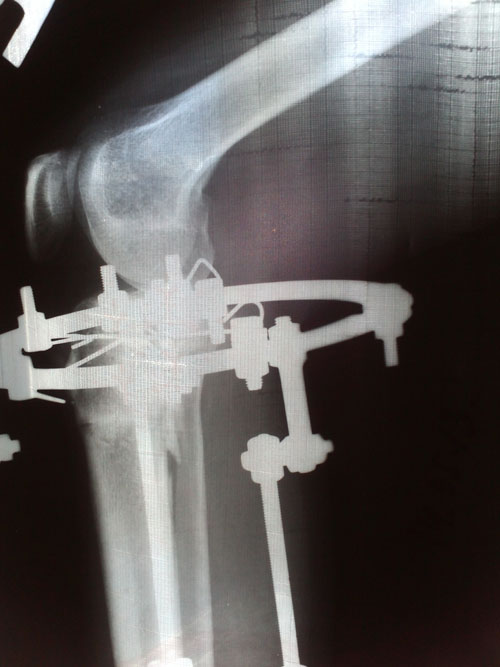

- Хирург: Онипко Н.Н.

- Диагноз: о-образная деформация нижних конечностей

- Дата операции.: 12.03.2013

38 дней с момента операции.

Ножки в норме, продолжаем фиксацию!

Дата операции 15.03.2013г.

Дата снятия аппаратов 17.05.2013г.

Срок лечения 62 дня.